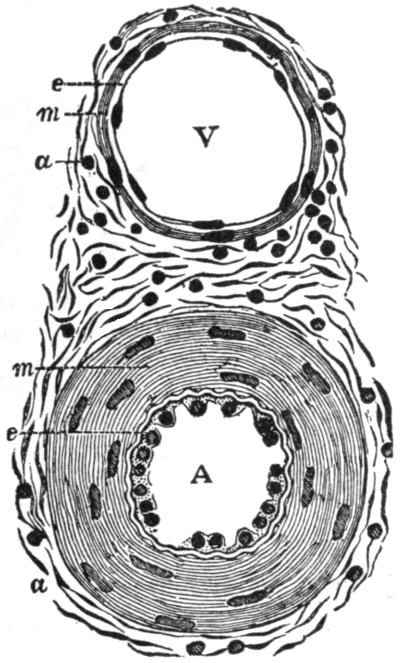

| V. | The Circulation | H 51 |